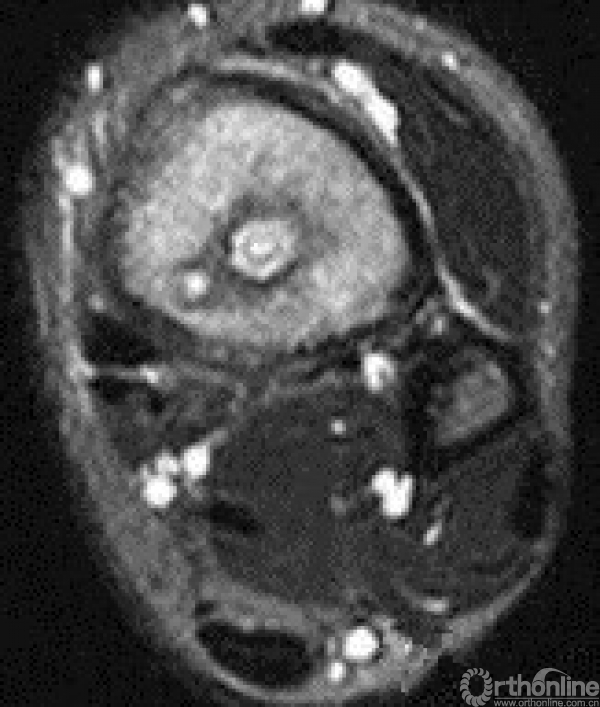

临床上常见反复发作,严重影响身心健康和劳动能力。急性骨髓炎起病时高热、局部疼痛,转为慢性骨髓炎时会有溃破、窦道形成、流脓、有死骨或空洞形成。重症患者可能会危及生命,有的不得不采取截肢的办法,致患者终生残疾。影像学和病理表现如下图。